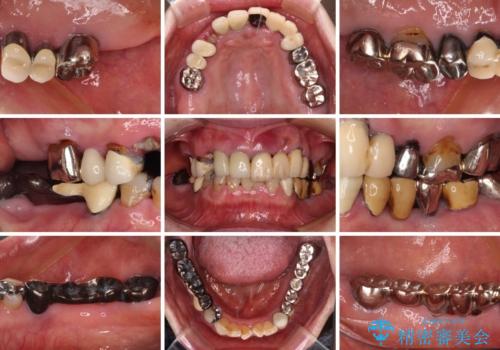

- 抜歯の必要な前歯や、以前治療した前歯のクラウンの外観を気にして来院された患者様です。

上顎犬歯や下顎大臼歯は、必要なところはインプラントを埋入することとしました。

クラウンが不適合であったり、根管治療の必要なほどの痛みのある歯であったり、見た目の気になる前歯などをオールセラミッククラウンに補綴治療を行うこととしました。